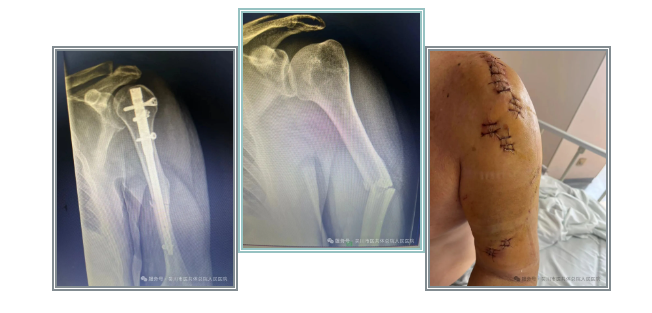

病例一:该患者为中年男性,外伤致肱骨干闭合性骨折,给予肱骨干骨折闭合复位髓内钉内固定术。髓内钉,顾名思义是一种置入骨髓腔内的内固定装置。它的工作原理就像是在长管状骨的内部架设一支坚固的支架,将断裂的骨头连接固定在一起。